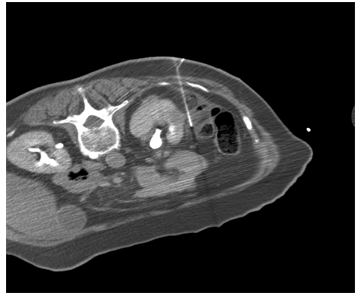

The numbers of patients treated with percutaneous techniques are increasing as the techniques are getting refined [20]. This approach is best suited for tumours located in the posterior or inferior aspect of the kidney. General anaesthesia is still employed in many centres, as it is uncomfortable for patients to lie still for long periods of time during the treatment. The technique of saline dissection to displace the bowel lying adjacent to kidney, used by expert interventional radiologists, has enabled safe and effective treatment of anterior and superior pole renal tumours (Figure 2). The technique is most commonly performed using Computerized Tomography (CT) scan guidance and less commonly using Magnetic Resonance Imaging (MRI) or ultrasound (US) guidance. The percutaneous approach is associated with lesser hospital stay than laparoscopy and is much safer for patients with significant comorbidity. New imaging modalities are emerging to help improve probe placement and real time intraoperative monitoring. For example, Real-time Virtual Ultrasonography (RVS) is a new modality that utilizes pre-operative CT scan data concomitantly with real time intraoperative ultrasonography. It is a promising tool, to mitigate the deficiencies of conventional ultrasound imaging, including limited visibility and inability of the ultrasound waves to travel through the ice produced bycryoablation [21].

Figure 2: CT-guided cryoablation of a small renal mass using the saline dissection method.